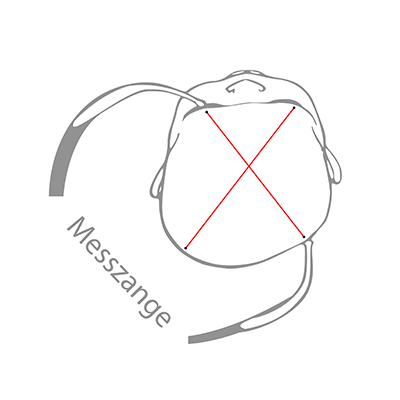

Lege dein Kind auf den Rücken. Blicke von oben (aus der Vogelperspektive) auf den Schädel. Hebe den Kopf deines Babys etwas an und richten ihn so aus, dass er gerade liegt, die Nase also nach oben zeigt. Beurteile nun die Kopfform deines Babys:

- Ist eine Hinterkopfseite abgeflacht?

- Steht auf einer Seite das Ohr weiter vorne?

- Ist auch die Stirnseite mehr vorgewölbt?

Je nach Ausprägung der Kopfasymmetrie treffen alle drei Aspekte zu. Bespreche mit deinem Kinderarzt das weitere Vorgehen und frage, ob er eine Lagerungstherapie für sinnvoll erachtet. Er wird auch die Differentialdiagnose durchführen und beurteilen, ob es sich tatsächlich um eine lagebedingte Kopfverformung handelt.